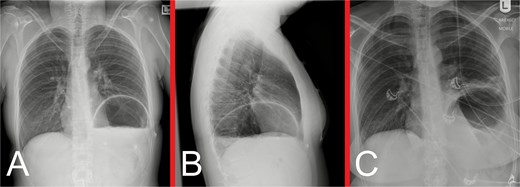

On initial examination, she was haemodynamically stable, with epigastric and left upper quadrant tenderness, but no peritonism. A venous blood gas showed a lactate of 2.7, but no acid–base disturbance or respiratory failure. Chest X-ray (CXR) revealed left hemidiaphragm effacement and a large air-fluid level in the left hemithorax (Fig. 1). A thoracoabdominal computed tomography (CT) scan revealed a markedly dilated stomach displaced into the left hemithorax, suggestive of a large, incarcerated left DH (Fig. 2). A nasogastric tube (NGT) was inserted for immediate gastric decompression (Fig. 1). An emergency gastroscopy confirmed a DH with displacement of the whole stomach into the chest. Endoscopic pyloric cannulation was impossible due to the herniated stomach’s configuration, but there was no mucosal damage, transmural necrosis, or gastric volvulus. Therefore, NGT decompression was continued as a temporizing measure, with planned semi-urgent definitive repair within a few days.

(A) Anteroposterior and (B) lateral view CXRs taken during the patient’s initial presentation, demonstrating effacement of the left hemidiaphragm outline, with a large air-fluid level within the left hemithorax and no evidence of a pneumothorax. (C) Anteroposterior view CXR following urgent NGT insertion for gastric decompression with its tip projecting over the stomach, with associated compressive atelectasis of the left lung.